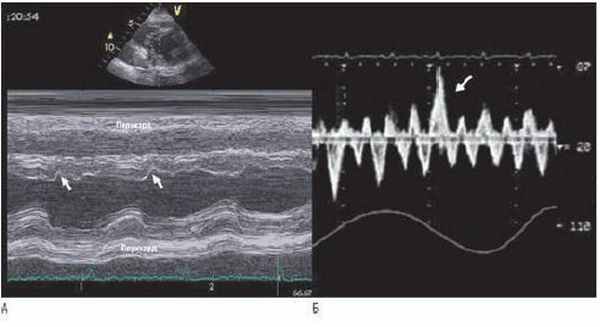

А - М-режим ЭхоКГ из парастернальной позиции. Представлены типичные особенности констриктивного перикардита, инцизура МЖП (показана стрелкой), и выравнивание задней стенки ЛЖ.

Б - запись пульсовой допплерографии печеночной вены. Диастолический поток увеличивается на выдохе (показано стрелкой).